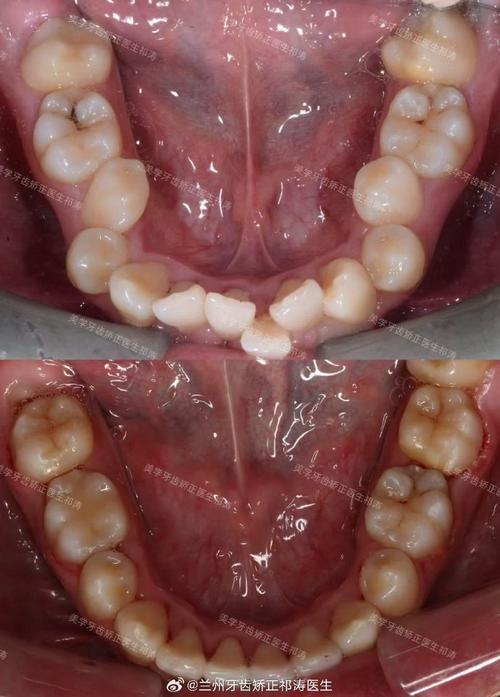

牙根裸露的本质是牙龈组织的退缩,使原本被牙龈包裹的牙根表面暴露出来,牙齿表面覆盖着一层牙釉质,是最坚硬的组织,但牙根表面覆盖的是牙骨质,下方连接着敏感的牙本质,一旦暴露,外界刺激(冷、热、酸、甜)容易通过牙本质小管传递至牙髓,引发敏感症状,在矫正牙齿时,牙齿需要在牙槽骨内移动,牙槽骨会随之发生改建——受压侧骨吸收,牵引侧骨增生,若矫正力度过大、移动速度过快,或患者自身牙槽骨条件较差(如骨量不足、骨质疏松),可能导致牙槽骨过度吸收,进而牵连牙龈组织,使其失去支撑而萎缩,形成牙根裸露。

除了矫正过程中的力学因素,其他原因也可能加剧牙根裸露,矫正前若存在未控制的牙周炎(牙龈炎进展到牙周组织感染),会导致牙槽骨 already 吸收,牙龈萎缩,此时矫正可能进一步加重问题;矫正期间口腔卫生维护不当,牙菌斑堆积引发牙龈炎症,长期炎症会破坏牙龈附着;个体差异(如天生牙龈薄、牙根形态异常)和不良习惯(如刷牙用力过猛、咬硬物)也是诱因。

若矫正期间已出现牙根裸露,需及时就医,轻度敏感可使用脱敏牙膏(含硝酸钾、氟化物成分),减少刺激;中度以上需进行牙周治疗,如龈下刮治清除牙菌斑、根面平整平整牙根表面,促进牙龈重新附着;严重牙龈萎缩可能需行牙龈移植术,从口腔其他部位(如上颚)取部分牙龈组织,覆盖暴露牙根,矫正医生会评估牙根吸收情况,必要时调整矫治力,避免进一步损伤。